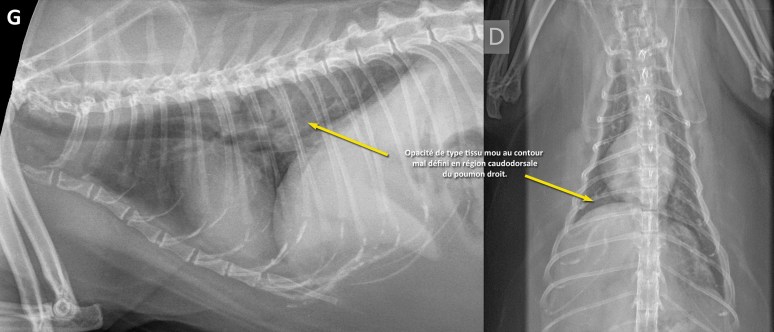

Comme la silhouette cardiaque était arrondie, on pouvait effectivement penser que l’augmentation d’opacité en région caudodorsale était associée à de l’oedème. Toutefois, les vaisseaux pulmonaires paraissaient normaux et la rondeur du coeur pouvait s’expliquer par la présence de gras péricardique chez ce patient obèse. Traiter avec un diurétique et recommander une échocardiographie restait toutefois une proposition valable. Compte tenu de l’âge de ce chat et de l’asymétrie de l’augmentation d’opacité pulmonaire, un processus tumoral devait aussi être envisagé. Une échographie aurait pu permettre de confirmer cette suspicion par le biais d’une cytoponction, si la masse se trouvait accolée à la paroi. Chez ce chat, une tomodensitométrie (CT, scanner) a été effectuée (images du bas) afin d’obtenir un portrait global des poumons et d’exclure la possibilité de métastases pulmonaires et abdominales. Une masse au contour irrégulier a été identifiée au lobe caudal droit, entourant une bronche principale aérée. Un carcinome bronchoalvéolaire a été fortement suspecté sur la base d’une cytoponction échoguidée. Le reste des poumons ne montrait pas de métastases franches, mais quelques foyers d’atélectasie… À suivre…